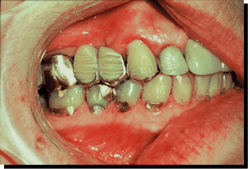

Fatigue is easily recognized in prostheses and restorative materials (figures 3 and 4).

The wavy patterns in amalgam are termed Luder lines or slip bands due to molecules in the alloy rearranging themselves from compressive strain.